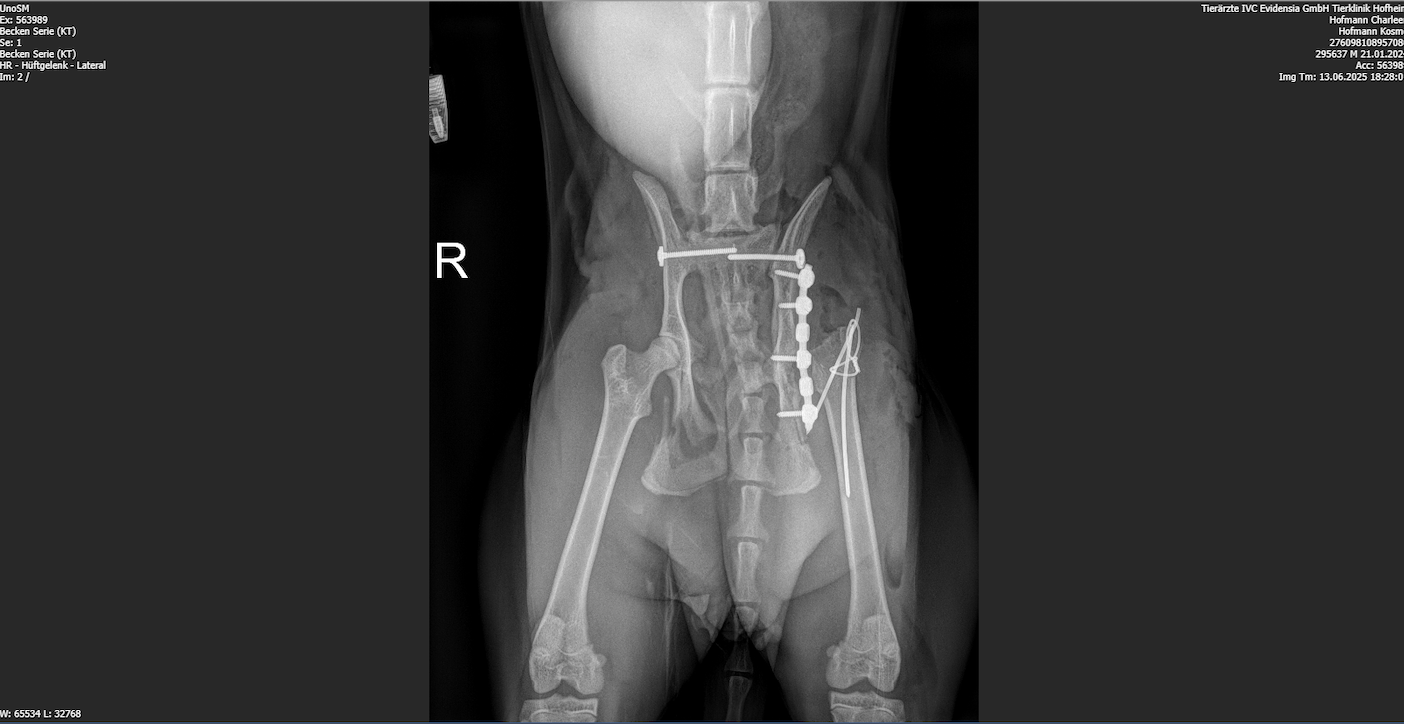

Die Bildgebung ergab multiple Beckenfrakturen, beidseitige Iliosakralgelenksluxationen, eine Beteiligung des linken Acetabulums, eine Läsion des linken Femurkopfes sowie eine mögliche Schwanzablösung im Bereich der ersten beiden Schwanzwirbel. Am Folgetag erfolgte die operative Versorgung mit bilateraler Stabilisierung der Iliosakralgelenke, Versorgung der Iliumfraktur inklusive Trochanter-Osteotomie und einer Femurkopf-Hals-Resektion links. Fünf Tage später wurde Kosmo zur physiotherapeutischen Erstvorstellung überwiesen.